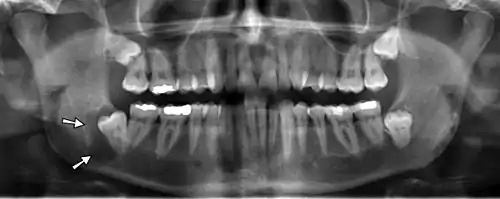

| Denigerous cyst of the right jaw around an impacted wisdom tooth | |

As the epithelial lining is derived from the reduced enamel epithelium,[22] on radiographic examination, a dentigerous cyst appears as a unilocular radiolucent area that is associated with just the crown of an unerupted tooth and is attached to the tooth at the cementoenamel junction. Dentigerous cysts may also involve odontomas, which by their nature also have tooth crowns. The radiolucency is generally well defined and well corticated. The radiolucency often have a sclerotic border indicating bony reaction, but a secondarily infected cyst may display ill-defined borders. However, a large dentigerous cyst may give the impression of a multilocular process due to the persistence of bone trabeculae within the radiolucency.

The radiographic distinction between an enlarged dental follicle and a small dentigerous cyst can be difficult and fairly arbitrary. Generally, any pericoronal radiolucency that is greater than 3–4 mm in diameter is considered suggestive of cyst formation.